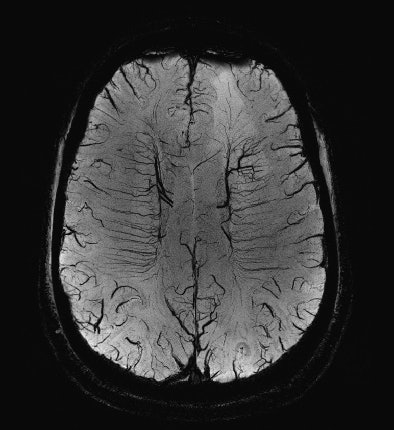

| A susceptibility-weighted image (SWI) with high spatial resolution illustrating the very small normal veins in the white matter of the brain. Note that on the left a malignant brain tumor is visible as a hyperintense lesion in the background. |